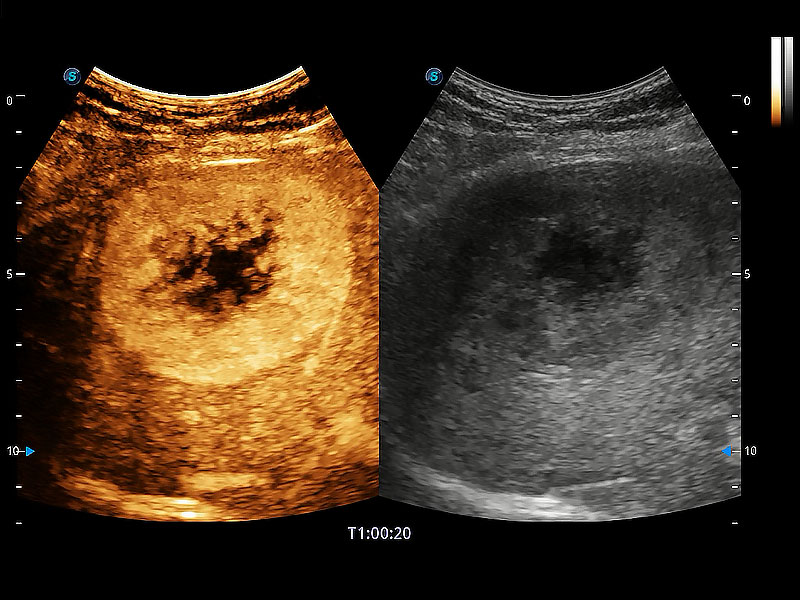

(犬)肝脏

(犬)胎儿主动脉弓立体血流

(犬)肾脏显微血流